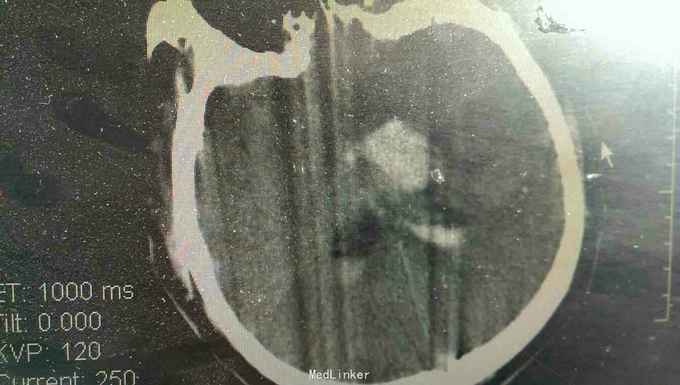

患者男性,56岁。以突发头痛伴意识不清半小时入院。患者入院半小时前突然自觉头痛,性质剧烈,呕吐多次,随即意识不清。来我院就诊。

浅昏迷状态,无语言。刺激后右侧肢体不动,左侧肢体可动。双侧瞳孔等大正圆,直径3.0毫米,光反射迟钝。右侧病理反射阳性。

脑出血,高血压病 急诊行微创硬通道内镜下血肿清除术,术中清除大部分血肿,患者术后第二天清醒右侧肢体三级,语言迟缓。